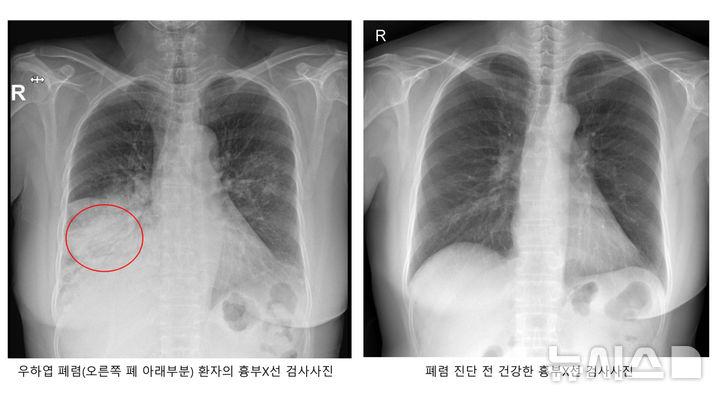

폐렴은 세균 또는 바이러스가 폐로 침투해 염증이 생긴 병이다. 폐렴구균으로 인한 세균성 폐렴이 흔하다. 폐렴구균은 평소에도 코와 목의 점막에 상주한다. 우리 몸의 면역력이 약해지면 폐, 뇌, 혈관, 귀까지 침투해서 폐렴, 수막염 등을 일으킨다.

폐렴의 초기 증상은 발열, 기침, 가래 등 일반 감기와 비슷하다. 하지만 폐렴구균이 본격적인 활동을 시작하면 고열과 기침, 가슴통증, 호흡곤란을 유발한다. 숨이 가빠지면 호흡수도 많아져 분당 20회를 초과한다.

폐렴구균이 원인인 폐렴일 경우 가래의 색깔이 적갈색으로 진하게 바뀌는 경우도 있다. 폐렴으로 인해 폐가 손상되게 되면 산소교환 기능이 저하되고, 혈액 속 산소 농도가 떨어진다.